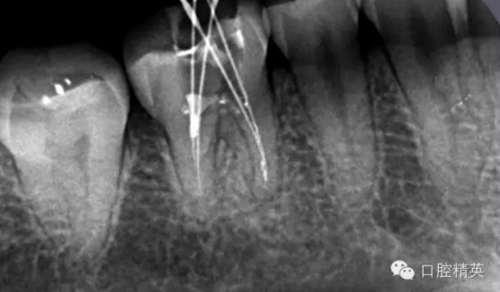

近舌8號(hào)k挫疏通,根尖部彎曲,我花費(fèi)時(shí)間2小時(shí)疏通。我個(gè)人覺(jué)得根管能否被疏通,第一個(gè)重要因素是時(shí)間,因?yàn)樽鳛檠荔w牙髓的醫(yī)生,首先就是需要的就是耐心。我個(gè)人覺(jué)得耐心是非常重要,因?yàn)楹芏喔鼙皇柰〞r(shí),都是我們快要放棄的時(shí)候。所以我每次都會(huì)安慰自己快好了,快好了,就差一點(diǎn)點(diǎn),在堅(jiān)持一會(huì)兒就好了。可以說(shuō)沒(méi)有耐心,想做好牙體牙髓,我個(gè)人覺(jué)得很難很難。第二個(gè)就是手法,不知道大家啟用挫是什么挫,一般我個(gè)人認(rèn)為,最好從8號(hào)開(kāi)始疏通,這樣不容易在狹窄的根管內(nèi)形成臺(tái)階(如果有條件的可以從6號(hào)開(kāi)始)。

這個(gè)病例難以疏通在于根中上段堵塞,根尖下段有臺(tái)階的形成,感覺(jué)不到彎曲的方向。首先我們處理根上段,我們可以采取的方法是先預(yù)備跟中上段,將它擴(kuò)開(kāi)來(lái),這樣有利于根尖下段的預(yù)備,建立良好的視野。對(duì)于根尖下段的臺(tái)階和彎曲 ,8號(hào)挫預(yù)彎,第二步要知道根管彎曲的方向,沿著根管彎曲的方向疏通。特別是有臺(tái)階的地方,一定不要硬來(lái),慢慢旋轉(zhuǎn)找到根管彎曲的方向(結(jié)合x(chóng)線片)避開(kāi)臺(tái)階,一定要記住慢慢旋轉(zhuǎn)角度越小越好,正旋逆旋找“緊點(diǎn)”,有經(jīng)驗(yàn)的醫(yī)生大概都知道,找到了“緊點(diǎn)”就等于找到了希望。手法一定要輕柔不易暴力!切記切記!戒浮戒躁(這句話也是特別要告訴我自己)。